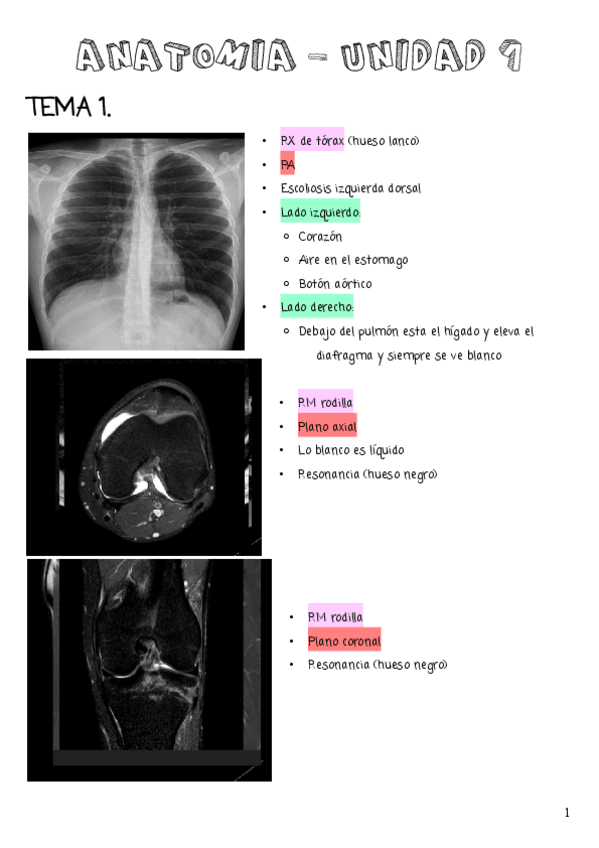

APUNTES UNIDAD 1 (TEMAS DEL 1 AL 7)

He publicado nuevos apuntes de Anatomía por la imagen: APUNTES UNIDAD 1 (TEMAS DEL 1 AL 7)

IMAGENES-UNIDAD-1.pdf

UNIDAD-1.pdf